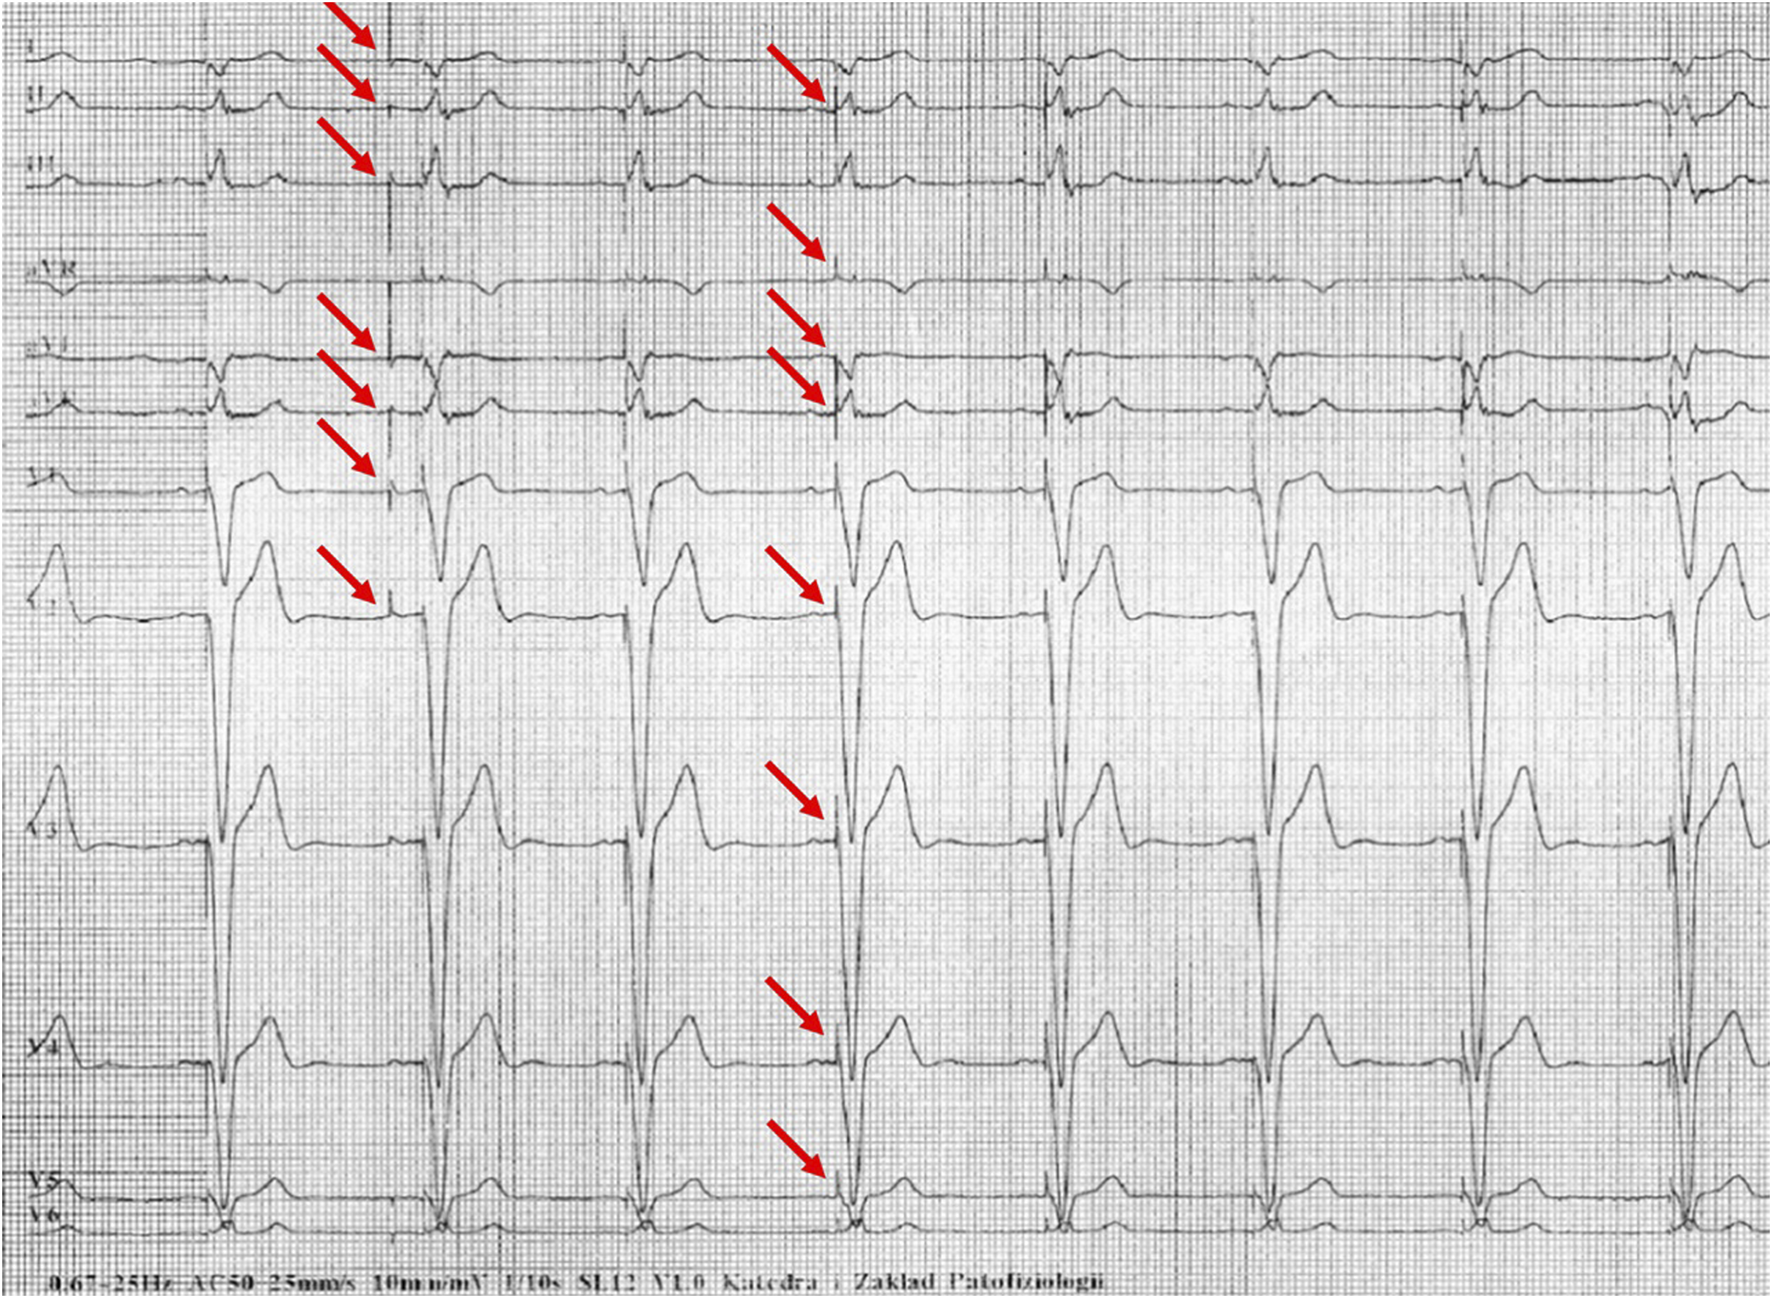

Figures 1–5 present a sample of ECGs incorrectly interpreted by the device. There are cases of pathologies commonly identified by clinicians. In Figure 1, we identified the dual-chamber pacing with a dual response (DDD) stimulation interpreted as atrial fibrillation and RBBB, so in this case, we have both overinterpretation and failure of recognition. A similar situation is presented in Figure 2, where we found the lack of atrial fibrillation diagnosis and at the same time overinterpretation with type 1 and 2 atrioventricular block. In Figure 3, the situation is presented where, instead of DDD pacing, LBBB and the atrial rhythm were proposed. Moreover, in Figure 4, the compensatory pause after premature ventricular beats was overinterpreted as atrioventricular Mobitz type II block. Finally, in Figure 5, we again identified the lack of proper diagnosis of the first-degree atrioventricular block, together with the overinterpretation of atrial fibrillation.

FIGURE 2

Example of incorrect interpretation by the device: Female, 70 years old. Coarse atrial fibrillation described by the device as sinus rhythm with first-degree atrioventricular block, Mobitz type I second-degree atrioventricular block (Wenckebach) and premature ventricular beats (25 mm/s, 10 mm/mV).